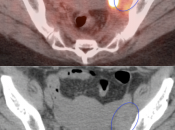

Cervical Cancer

Fast Facts:

- 2nd most common cancer in women worldwide

- Localized Disease: 5-year survival: 91%

- Distant Disease: 5-year survival: 16%

- Squamous cell carcinoma > 90%

- Adenocarcinoma 5-9%

Initial Staging:

- Valuable diagnostic tool for locally advanced disease, to determine nodal status and potential distant metastatic disease (if no evidence of regional or distant disease, initial management is surgical).

- PET/CT has high sensitivity (>80%) and high specificity (>90%) for metastatic lymph nodes ≥ 8.0 mm.

- Nearly every cervical cancer ≥ 8.0 mm is intensely FDG avid (MRI, however, is still considered the best modality for evaluating tumor size and invasion).

Metastatic Disease:

- Direct invasion of adjacent structures.

- Lymphatic spread to pelvic and retroperitoneal lymph nodes.

- Hematogenous spread, often to lungs, liver, and bone.

False Negatives:

- Primary lesions < 8.0 mm (beneath the resolution of PET)

- Nodes or metastatic deposits < 8.0 mm

False Positives:

- Post-radiation inflammatory changes